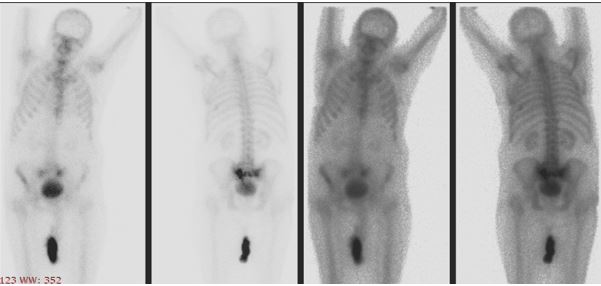

לשבר של עצם העצה קיימים שלושה מרכיבים, והשיטה מתבססת עליהם: שתי עצמות ארוכות, ועצם אחת רוחבית, שכאשר אחד מהם ניזוק הוא משפיע על כולם ומכאן נובעים הכאבים. הסיבות למחלה בדרך כלל הם בריחת סידן ולעיתים נדירות יכולה לבא מחמת טראומה כרונית. אם רוצים לטפל בבעיה חייבים לטפל בשלושת העצמות בו זמנית, אחרת הטיפול יכשל והמטופלים ימשיכו לסבול קשיים וכאבים בהליכה.

מחדירים ארבעה מחטים תחת שיקוף לעצם העצה, ביניהם מתחבא בלון זעיר המתנפח בעודו במחט, לאחר חדירת המחטים מסירים את הבלון, ובחלל שנוצר במקום הבלון מחדירם צמנט אורתופדי, המתקשה במהירות וככה הוא מייצב את עצם העצה ומפחית ברמה משמעותית את הכאבים.

אם כבר הגעתם בשיבה טובה לגיל השלישי, ומרגישים קשיי הליכה וכאבים חזקים באזור האגן בפרט בעת הישיבה, יתכן מאד שאתם סובלים ממחלה זו של שברי אי ספיקה בעצם העצה. אנו ממליצים לכם לגשת לרופא בזריזות, בכדי למנוע סבל מיותר. מידע מוקדם על המחלה יכול לשפר משמעותית את רמת הכאב, החיים ואת הטיפול בה.